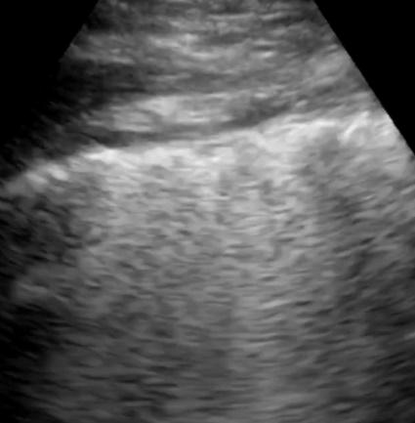

Most deep neural networks (DNNs) based ultrasound (US) medical image analysis models use pretrained backbones (e.g., ImageNet) for better model generalization. However, the domain gap between natural and medical images causes an inevitable performance bottleneck. To alleviate this problem, an US dataset named US-4 is constructed for direct pretraining on the same domain. It contains over 23,000 images from four US video sub-datasets. To learn robust features from US-4, we propose an US semi-supervised contrastive learning method, named USCL, for pretraining. In order to avoid high similarities between negative pairs as well as mine abundant visual features from limited US videos, USCL adopts a sample pair generation method to enrich the feature involved in a single step of contrastive optimization. Extensive experiments on several downstream tasks show the superiority of USCL pretraining against ImageNet pretraining and other state-of-the-art (SOTA) pretraining approaches. In particular, USCL pretrained backbone achieves fine-tuning accuracy of over 94% on POCUS dataset, which is 10% higher than 84% of the ImageNet pretrained model. The source codes of this work are available at https://github.com/983632847/USCL.